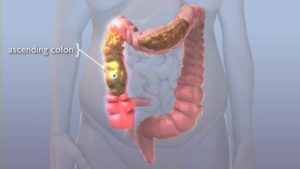

Уплотнение образований в кишечно-желудочном тракте, которые имеют овальную или округленную форму, называют каловой пробкой. Наличие пробок может быть одиночным или множественным.

Размеры калового камня от 100 мл до 300 мл и больше, но слишком большие габариты образований в прямой кишке встречаются редко.

Каловый камень может возникнуть при опускании толстой кишки, а также, если у больного имеются трудности с продвижением кала, что связано с деформацией кишки.